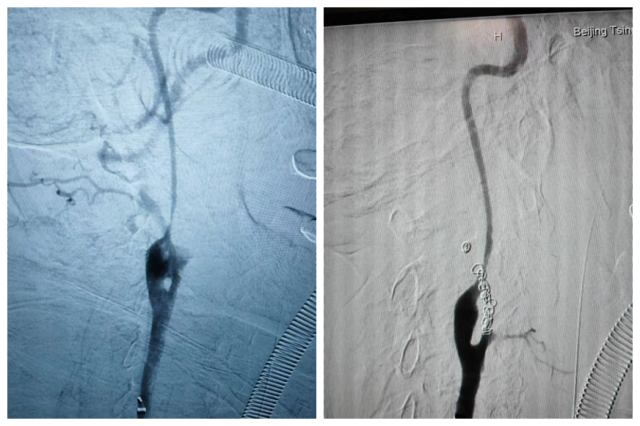

动脉造影可见颈外动脉造影剂外溢,栓塞后止血

患者从急诊紧急接入手术室,就在此时,患者突发心脏骤停,血管外科、麻醉科、耳鼻咽喉头颈外科医师齐上阵,立即对患者实施抢救,三名医师轮流为患者进行心肺复苏数轮,患者逐渐恢复了自主心律。在麻醉科的保障下,血管外科曹战江医师、蒋超医师、李子澎医师联合手术,行股总动脉穿刺,造影可见颈外动脉被肿瘤侵犯破裂出血,行动脉栓塞后,出血最终止住了,患者的血压同步恢复稳定,转至重症监护病房。